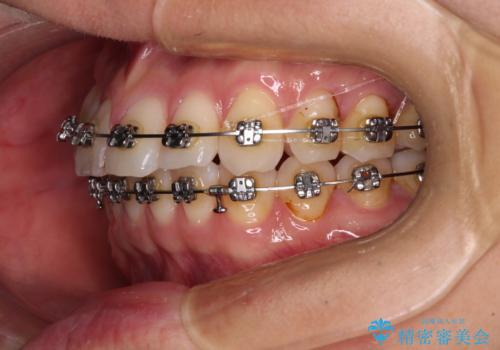

- 矯正装置

- メタルブラケット

咬合平面改善のため、アンカースクリューを多用し、ワイヤー装置にて矯正治療を行うこととしました。